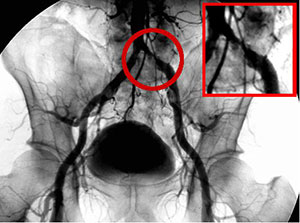

末梢血管形成術(EVT)

下肢の血管の動脈硬化に対する治療も、近年さかんに行われるようになりました。当院でも骨盤部・大腿部・膝下の各部に対するカテーテル治療が施行可能です。 病変が広範囲の場合は手術治療も選択可能ですし、重症例に対する血管再生治療についても検討可能です。またこれらの多彩な治療選択を組み合わせることで、よりよい効果を得ることも期待されます。